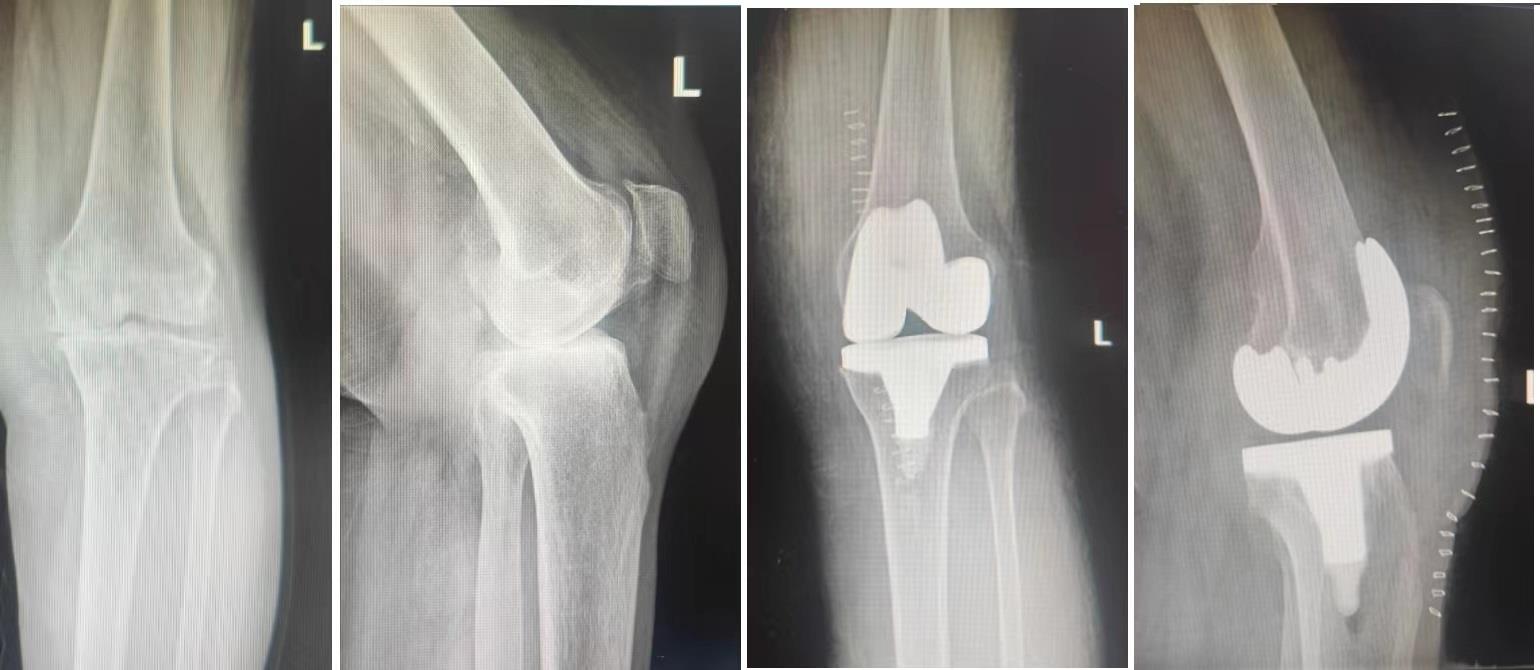

目的 比较CR假体与PS假体在人工膝关节置换术后应用效果。 方法 随机选取2021年6月至2022年6月在我科收治且符合选择标准的膝骨性关节炎患者64例,随机分为观察组和对照组(n = 32)。观察组使用CR假体实施TKA,对照组使用PS假体实施TKA。记录两组患者的手术时间、术后引流量、手术前后HGB差值、术后住院时间,术后7 d、14 d、45 d、3个月、1年膝关节ROM、VAS评分、HSS评分、膝关节最大前后向位移,并定期复查X线片。 结果 两组患者在手术时间、术后住院时间、VAS评分、膝关节最大前后向位移方面相当;和对照组相比,观察组术后引流量明显更少,差异有统计学意义(P < 0.05);和对照组相比,观察组在HGB差值上明显更低,差异有统计学意义(P < 0.05);手术之前两组患者ROM、HSS评分无明显差异,和观察组比较,术后7 d、14 d、45 d时对照组ROM以及HSS评分更高,差异有统计学意义(P < 0.05),术后3个月时,两组ROM、HSS评分相当,术后6个月、1年时观察组的ROM、HSS评分明显更高,差异有统计学意义(P < 0.05)。 结论 CR假体在手术失血量和术后引流量方面优于PS假体,可以降低手术风险,两种假体在术后均可获得良好的膝关节稳定性,而PS假体早期临床效果较好,CR假体长期临床效果更优。

Objective To compare the effect of posterior cruciate ligament retaining (CR) and posterior cruciate substituting (PS) prosthesis in knee arthroplasty. Methods 64 patients with knee osteoarthritis were admitted to our department from June 2021 to June 2022 and whom met the selection criteria were randomly selected and divided into observation group and control group (n = 32). CR prosthesis was used in the observation group, and PS prosthesis was used in the control group. Operation time, postoperative drainage volume, difference of hemoglobin (HGB) before and after operation, postoperative hospital stay, postoperative range of motion at 7 d, 14 d, 45 d, 3 months and 1 year were recorded. ROM, visual analog pain Scale (VAS), Hospital for special surgery (HSS) score, and maximum forward and backward displacement of knee joint and the regular radiographs were also recorded, too. Results The two groups were similar in terms of operation time, postoperative hospital stay, postoperative VAS score and maximum anterior and posterior displacement of knee joint, with P values greater than 0.05, which had no statistical significance. The postoperative drainage volume in the observation group was significantly less than that in the control group, with statistical significance (P < 0.05). The HGB difference of observation group was significantly lower than that of control group, with statistical significance (P < 0.05). There was no statistically significant difference in ROM and HSS scores between the two groups before surgery; the ROM and HSS scores of the control group at 7, 14 and 45 days after surgery was better than that of the observation group, with statistical significance (P < 0.05); the ROM and HSS scores of the two groups at 3 months after surgery was not statistically significant. The ROM and HSS scores in the observation group was better than that in the control group at 6 months and 1 year after operation, and the difference was statistically significant (P < 0.05). Conclusions CR prosthesis is superior to PS prosthesis in terms of intraoperative blood loss and post?operative drainage volume, which can reduce surgical risk. Both kinds of prosthesis can achieve good knee stability after surgery, while PS prosthesis has better early clinical effect, while CR prosthesis has better long?term clinical effect.